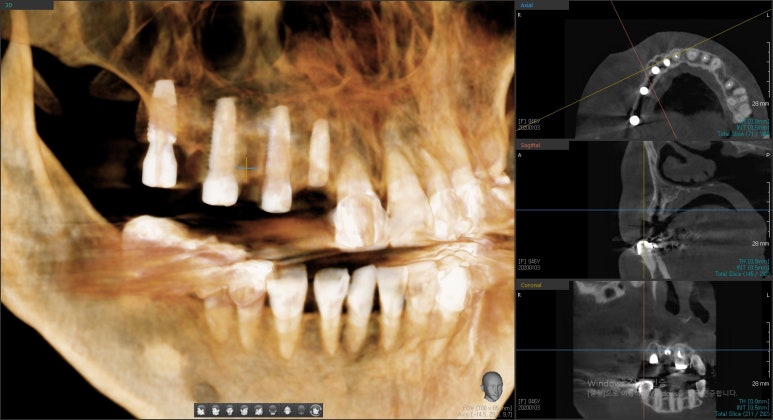

1.네비게이션 임플란트의 모의수술을 위해 3D구강스캔, CT를 먼저 촬영하였습니다.

- 이 구강스캔을 바탕으로 임플란트 모의수술이 디자인됩니다.